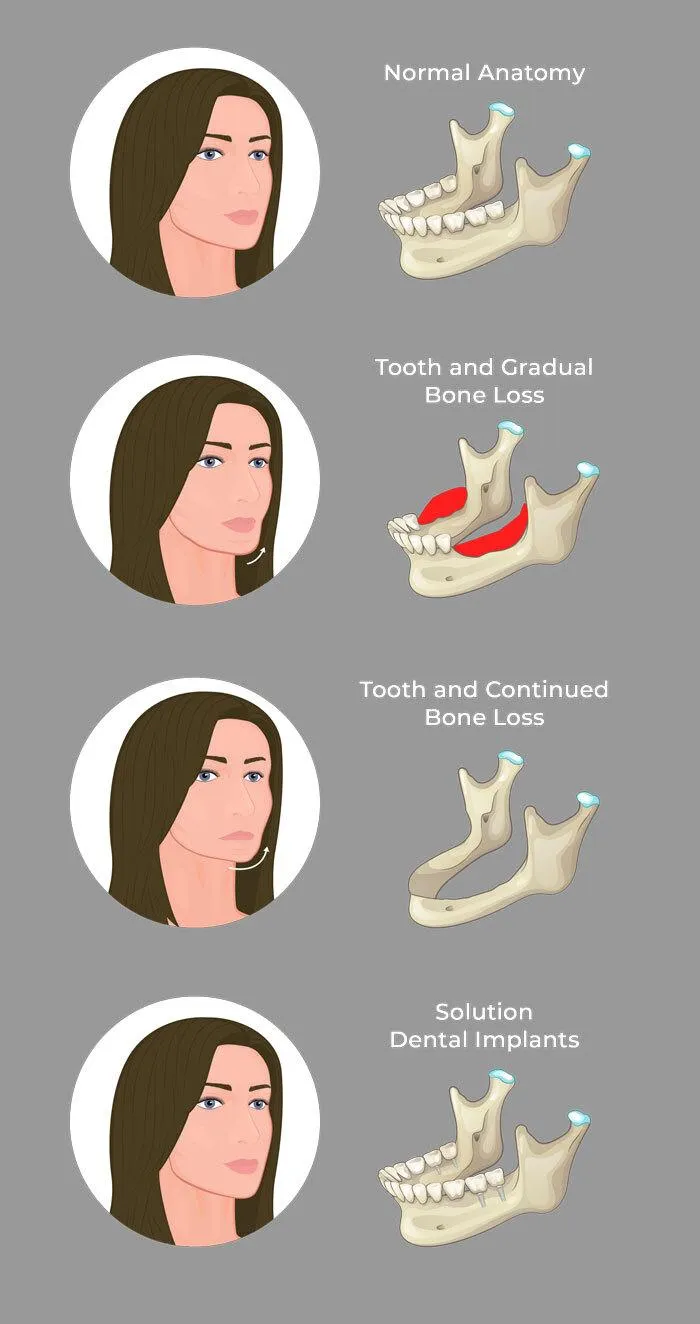

25% of Your Jaw Bone is LOST within the first year a tooth is missing

25% of Your Jaw Bone is LOST within the 1st year a tooth is missing

How Missing Teeth Affect Your Jaw Shape

If there isn't enough bone left, you will not be eligible for dental implants.

Patients have put off coming in... Only to later find out they were no longer eligible for dental implants because they had lost too much bone.

They told us... I would've paid any amount of money to go back in time and find out sooner!